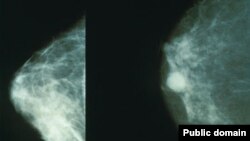

Иллюстрациялык сүрөт.